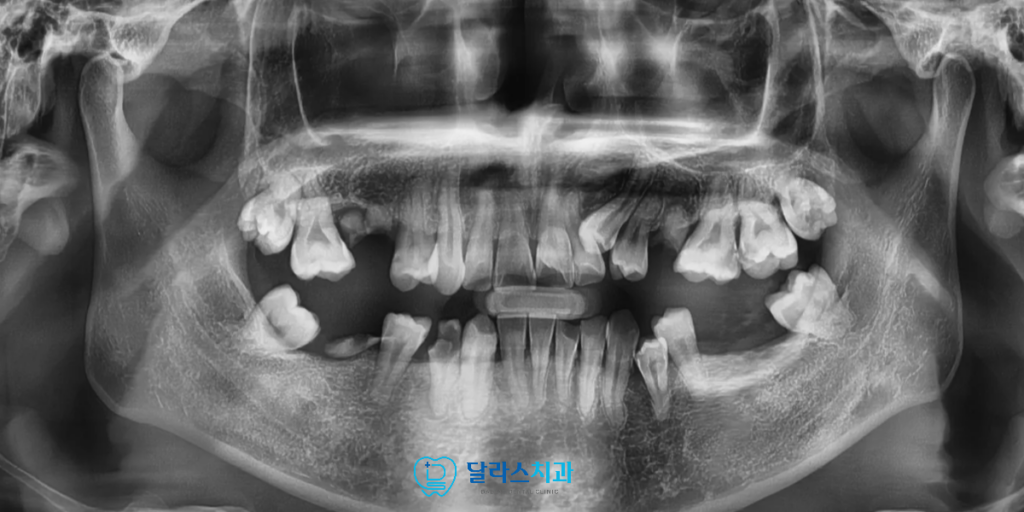

이번 환자분은 극심한 치과 공포증으로 인해

오랜 기간 치료를 미뤄오다 내원하신 30대 남성분이었습니다.

여러 치아가 충치로 손상되었거나 이미 발치된 상태였고

상실된 부위로 인해 어금니 교합이 되지 않으면서

입을 벌릴 때마다 옆에서 들릴 정도로 큰 소리가 나는 상황이었습니다.

이는 턱관절이 안정적인 위치를 잡지 못하고 있다는 신호로

전반적인 교합을 다시 정비해야 하는 상태였습니다.

초진 검사에서 앞니 쪽 치아가 심하게 겹쳐 있는 크라우딩이 확인되었고

아래 치아의 중심선도 틀어져 있어 단편적인 치료로는 진행이 어려운 상황이었습니다.